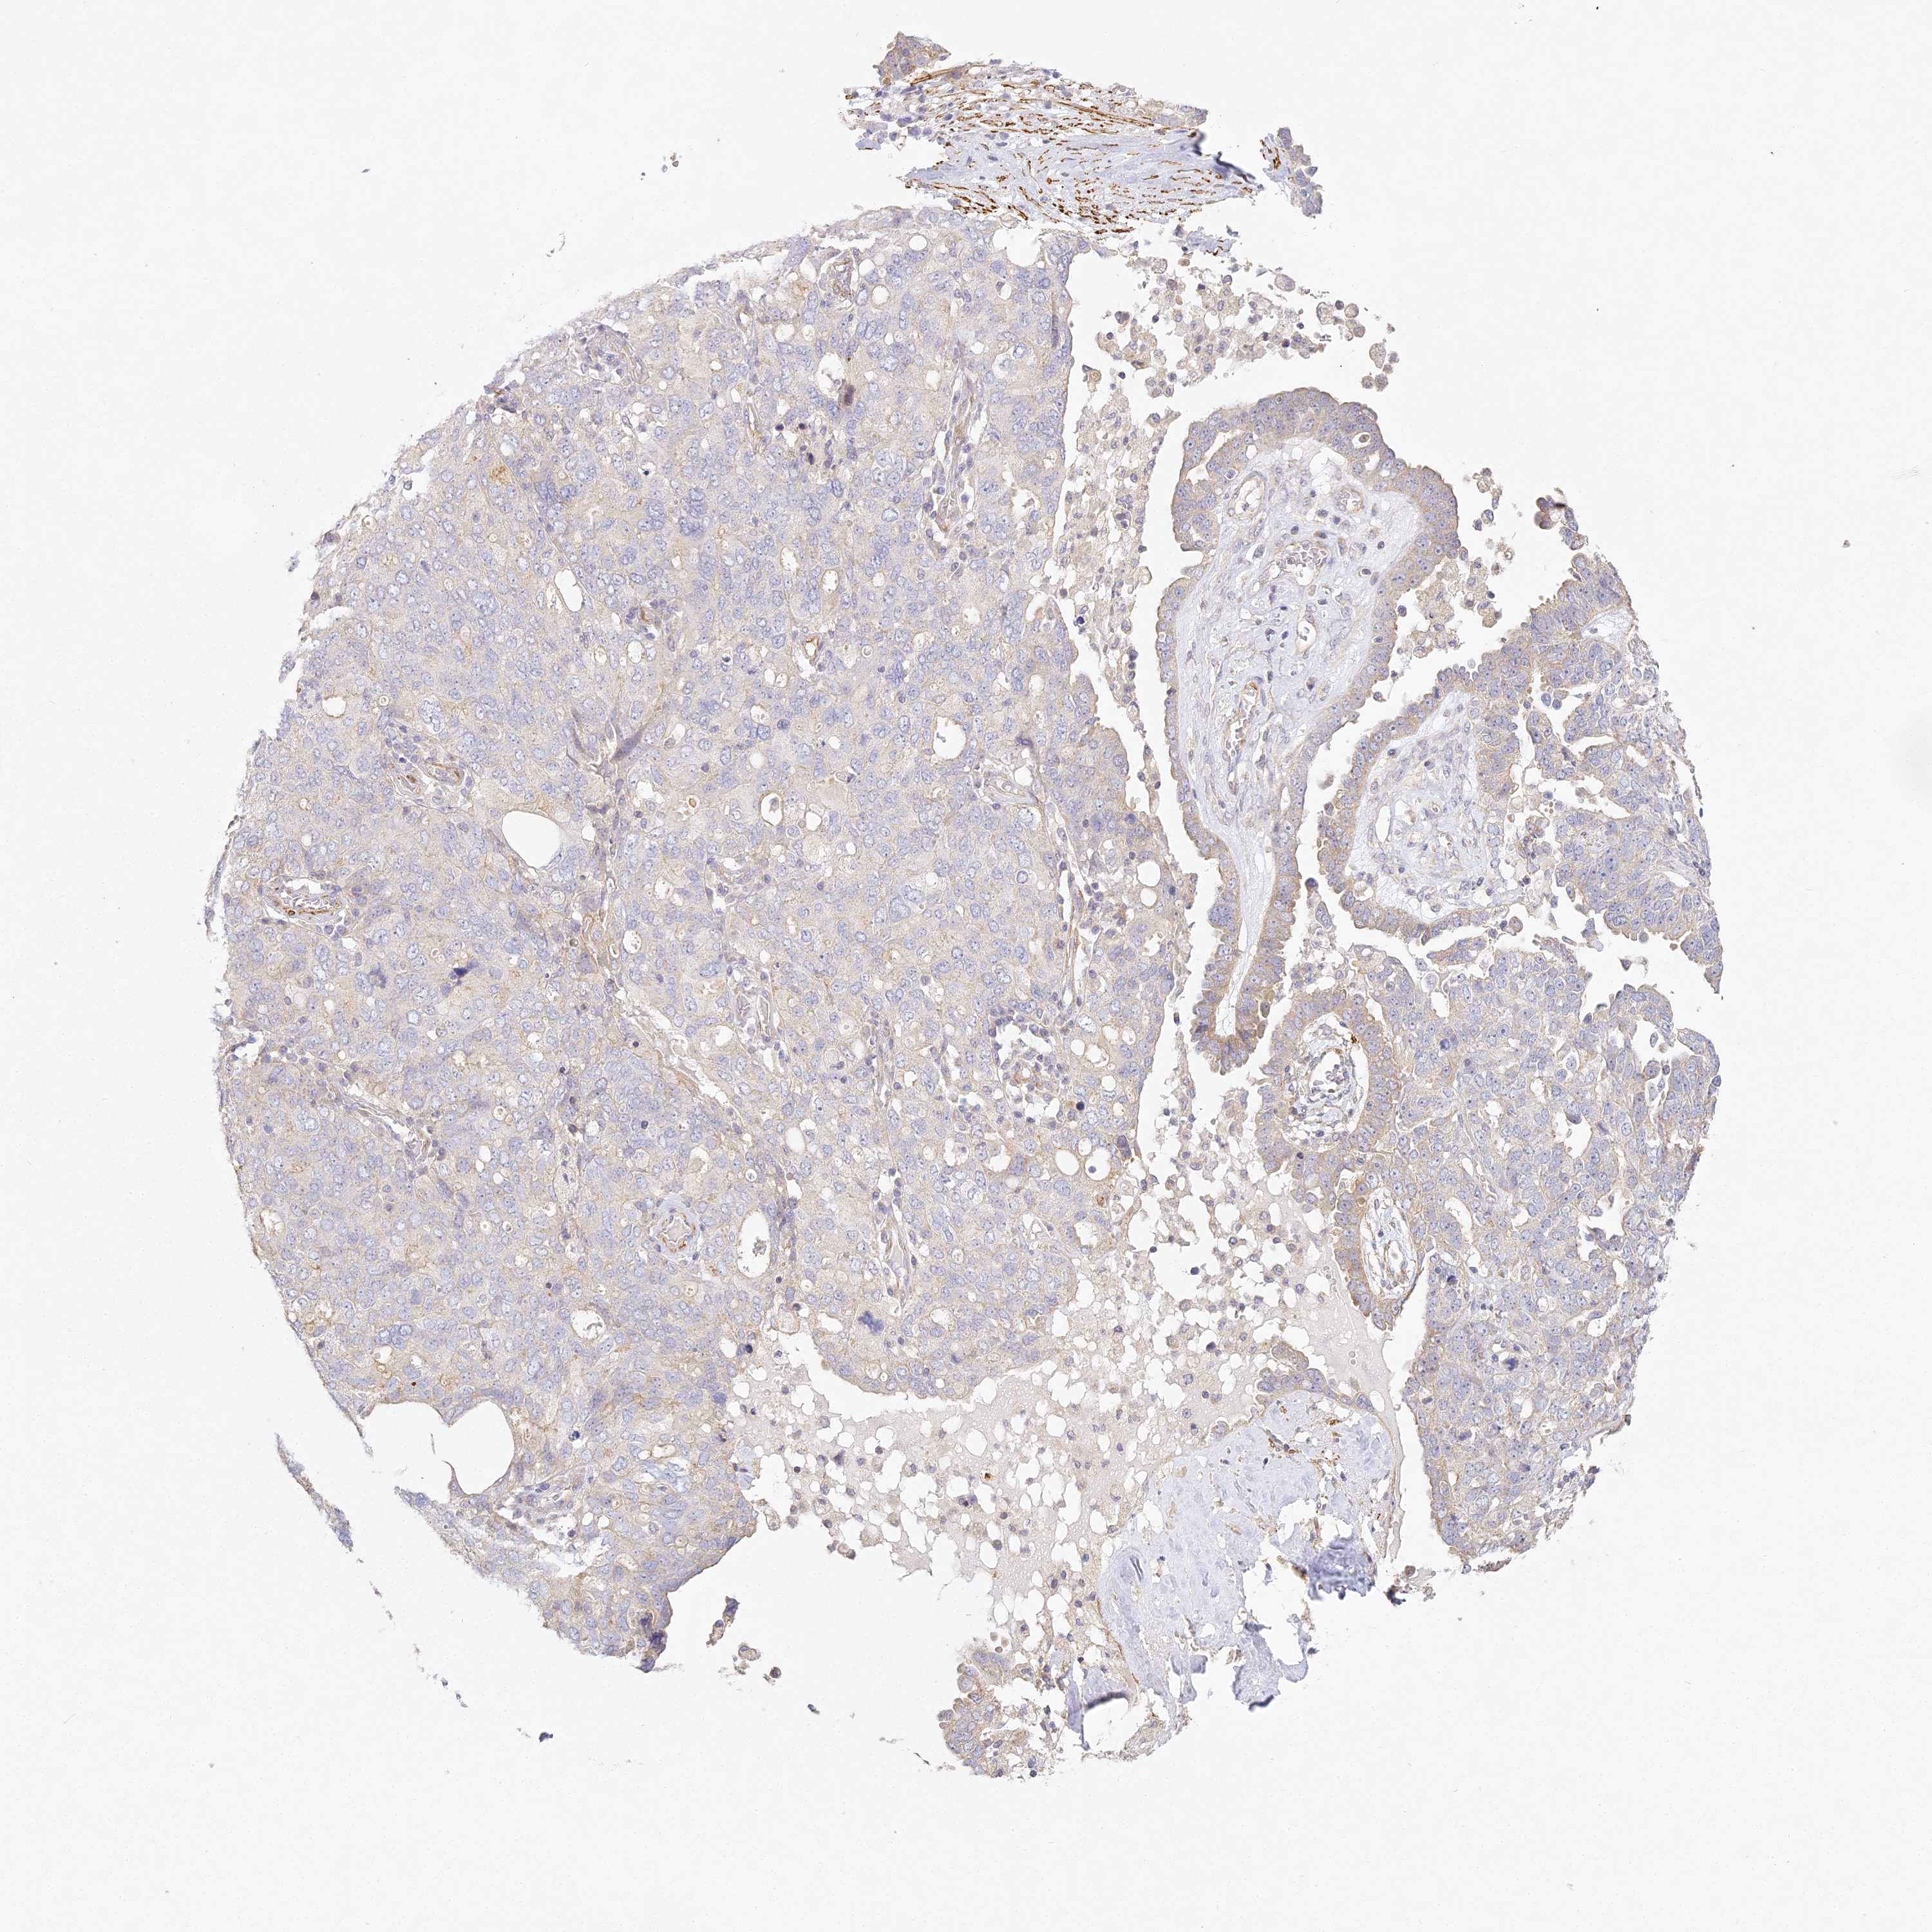

OVARIAN CANCER - Protein expressioni

A mouse-over function shows sample information and annotation data. Click on an image to view it in a full screen mode. Samples can be filtered based on level of antibody staining by selecting one or several of the following categories: high, medium, low and not detected. The assay and annotation is described here.

Note that samples used for immunohistochemistry by the Human Protein Atlas do not correspond to samples in the TCGA dataset.

Antibody stainingi

Antibody staining in the annotated cell types in the current human tissue is reported as not detected, low, medium, or high, based on conventional immunohistochemistry profiling in selected tissues. This score is based on the combination of the staining intensity and fraction of stained cells.

Each image is clickable and will lead to virtual microscopy that enables deeper exploration of all samples and also displays staining intensity scores, fraction scores and subcellular localization as well as patient and tissue information for each sample.

Antibody HPA035900

Antibody HPA035901

Carcinoma, endometroid